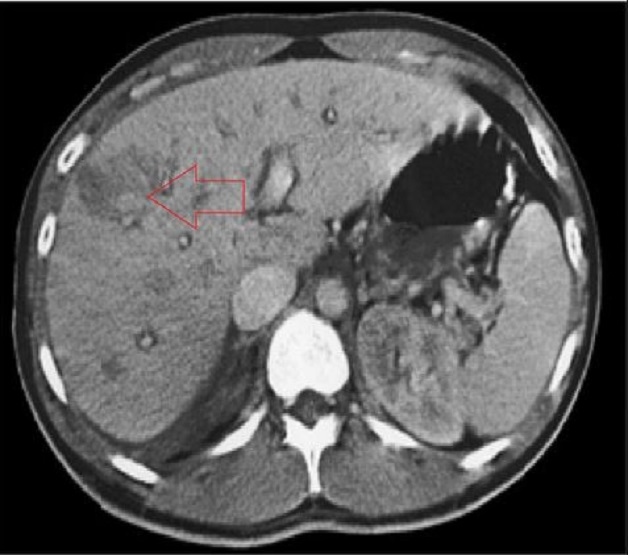

Mô tả tổn thương sán lá gan trên phim chụp cắt lớp vi tính (hình minh họa).

Siêu âm thấy có các ổ giảm hay hỗn hợp âm, hoặc giảm tỷ trọng trên chụp cắt lớp vi tính tập trung thành đám hình chùm nho trên cắt lớp vi tính, ít gặp hơn hình ảnh dày bao gan tương ứng với vị trí thương tổn hoặc hình ảnh tụ dịch quanh gan, dưới bao gan.